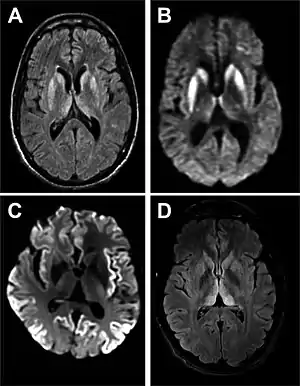

A DCJ é causada por proteínas denominadas priões.[4] Os priões são proteínas mal enoveladas que fazem com que proteínas corretamente enoveladas se tornem elas próprias desenoveladas.[3] Cerca de 85% dos casos ocorrem por razões desconhecidas, enquanto cerca de 7,5% dos casos são herdados de um dos progenitores de forma autossómica dominante.[3][5] A doença pode também ser transmitida por exposição ao cérebro ou tecidos da medula espinal de uma pessoa infetada.[3] Não há evidências de que possa ser transmitida entre pessoas por contacto normal ou transfusão de sangue.[3] O diagnóstico da doença requer que sejam descartadas outras potenciais causas e pode ser complementado por electroencefalograma, punção lombar ou ressonância magnética.[3]